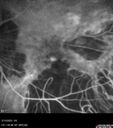

Prethreshold PDR right eye - mild NVD88 views

Prethreshold PDR right eye - mild NVD86 views